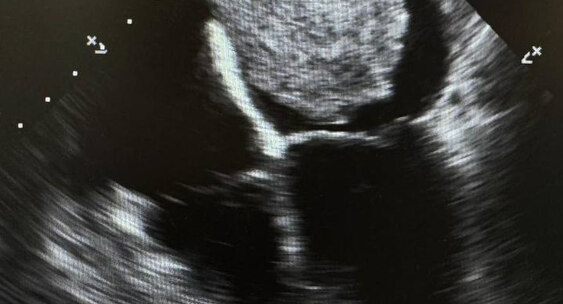

УЗИ сердца показало миксому размером 6,5x4,6 см, плюс недостаточность митрального и трикуспидального клапанов 2-3 степени.Коммерсантъ Кавказ